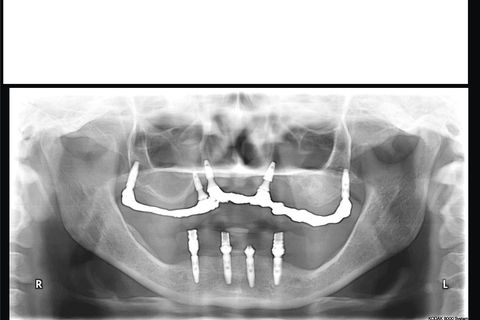

Panorâmica 8 meses pós op. Há uma pequena desadaptação da barra aos mini pilares devido a afrouxamento de dois parafusos que foi corrigido e apertados(havia um pequeno incremento metálico em um dos pilares - defeito de fundição)